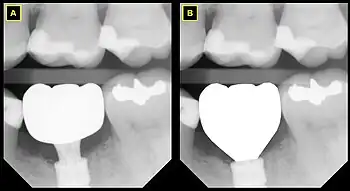

B This emergence profile respects the gingival architecture and emerges fully subgingivally.

In implant dentistry, running room refers to the apico-coronal distance between the platform of a dental implant and the gingival margin. It is a critical factor in restorative implant dentistry because it is effectively the "vertical distance [available subgingivaly] to make a transition from the smaller diameter prosthetic platform of an implant to the larger cross-sectional cervical shape of the tooth being restored."[1] The term was coined by Jonathan Zamzok, a Manhattan prosthodontist, in the late 1990s.[2]

Adequate running room is necessary to allow the implant-supported crown to exhibit a tooth-shaped contour despite the smaller diameter and circular nature of implant platforms.[3] For example, the mean mesial-distal dimension of a maxillary central incisor at the points at which it contacts the adjacent teeth is 8.6 mm, and the mean mesial-distal dimension of the same tooth at the cementoenamel junction (CEJ) is 6.4 mm.[4] Even though the implant diameter chosen for the maxillary central incisor is usually around 4–5 mm, the supragingival tooth contours need to mimic those of the natural tooth if esthetic success is intended.

As the anatomical crown and root tapers towards the apex, the mesial-distal dimension decreases, and so the mean mesial-distal dimension at the marginal crest of bone, which lies approximately 2 mm apical to the CEJ, is smaller. The tooth has the apico-coronal distance from the marginal crest of bone to the contact point in order to increase from the much narrower mesial-distal dimension to the greater mesial-distal dimension, and this distance is subgingival (below the gum line). Running room refers to this subgingival apico-coronal distance.

In general, it is recommended that implants be given approximately 3mm of running room in compliance with the rule of thumb that implants should be placed as deep as necessary and as shallow as possible.[5]